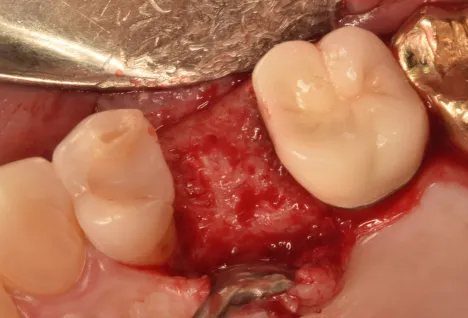

Dr.-Geivelis_Fig

Fig. 3. Cytrans® Granules (S size) and allograft immediately after placement in the socket.